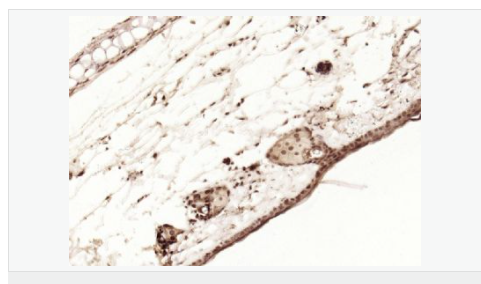

| 產(chǎn)品應(yīng)用 | WB=1:1000-2000 ELISA=1:1000-5000 IHC-P=1:100-500 IHC-F=1:100-500 Flow-Cyt=1ug/Test ICC=1:100-500 IF=1:100-500 (石蠟切片需做抗原修復(fù)) not yet tested in other applications. optimal dilutions/concentrations should be determined by the end user.  |

| 細(xì)胞定位 | 細(xì)胞核 細(xì)胞漿 |